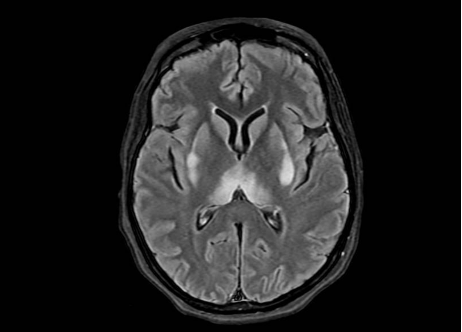

The patient’s imaging diagnostics were significant for a head CT that showed high-density foci in the globi pallidi, right greater than left, likely reflecting calcification (Figure 1) and a brain MRI completed on initial admission in late March that was significant for grossly abnormal subcortical enhancement with associated T2/Flair hyperintensity noted in the bilateral medial thalami, posterior putamen, midbrain, substantia nigra, and periaqueductal gray matter (Figure 2). On initial admission, clinicians performed an EKG, which was significant for diffuse T-wave inversions in the inferior and precordial leads (e.g. cerebral T-waves) that resolved on repeat testing (Figure 3).

Figure 2. MRI Brain (with and w/o contrast) on day of initial admission before treatment. MRI Brain showing symmetric restricted diffusion with associated T2/FLAIR hyperintensity noted in bilateral medial thalami, posterior putamen, midbrain (including the substantia nigra) and periaqueductal gray. Additional subtle T2/FLAIR hyperintensity without corresponding restricted diffusion noted dorsal medulla. No associated enhancement.